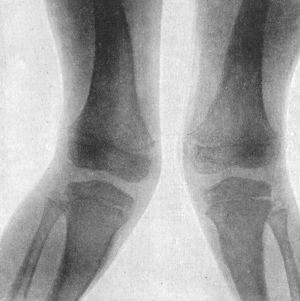

| 138. | Radiogram of Case of Double Genu Valgum in a Child | 268 |

| 139. | Genu Valgum in a Child. Patient standing | 269 |